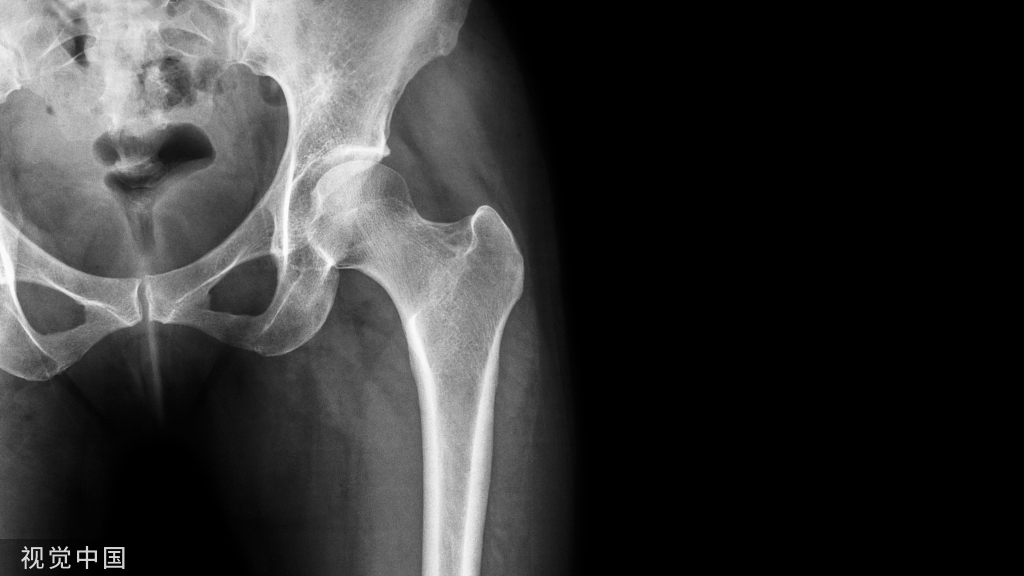

骨盆详细体格检查方法!

在检查骨盆前,检查者必须首先检查腰椎和髋关节,腰椎和髋关节有问题也会导致骶髂部位的牵涉痛。因为骶髂关节部分是韧带关节,与其他外周关节的活动度相比,骶髂关节的活动度比较小。需要指出的是,任何导致骶骨和髂骨相对位置改变的因素,均可引起耻骨联合相应的位置改变。